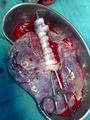

للمشيمة وجهان ومحيط: وجه رحمي محدب أحمر مدمى مزغب لامع عليه أثلام تقسمه فصوصاً تدعى فلق المشيمة cotyledon عددها 15-30 فلقة، ووجه جنيني أملس يستره غشاء شفاف يسمى الغشاء الأمينوسي amnion يرتكز السرر على هذا الوجه وترى عليه تشعباته وتوزعها بين الفلق المشيمية.